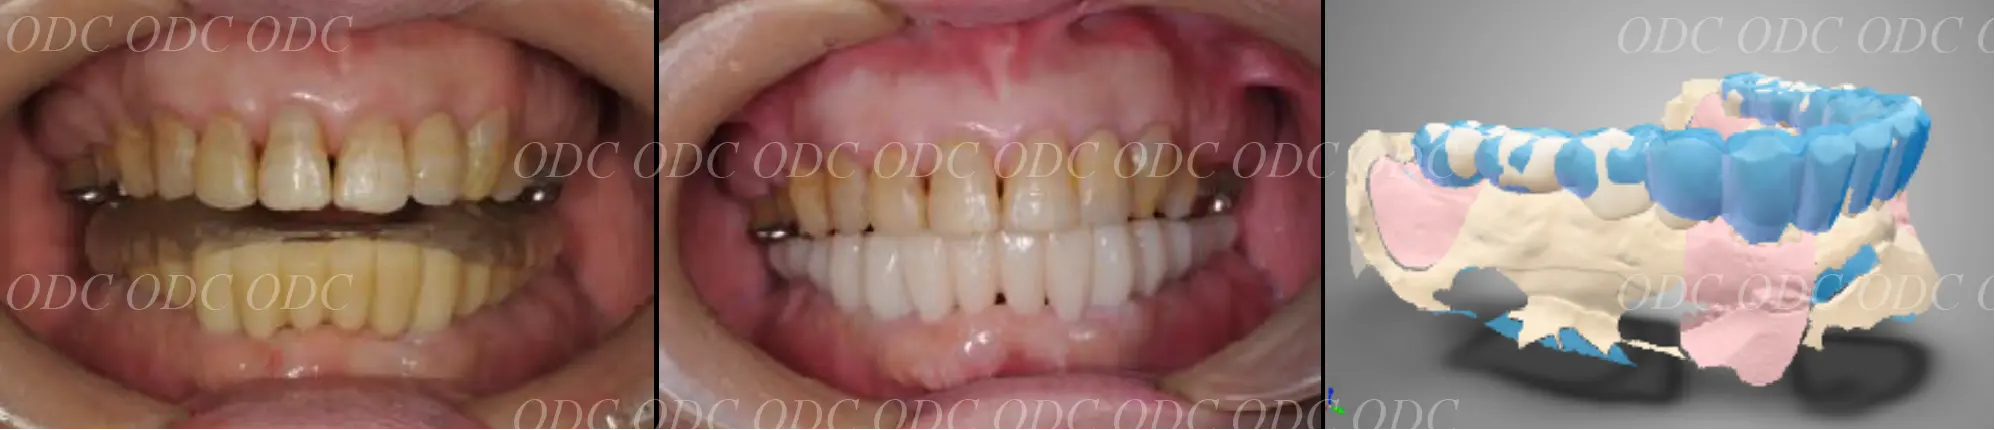

2011年、噛めないという主訴で65歳の男性が来院されました。

全顎的な治療を希望されていましたので、口腔内はもちろん骨格・顔貌・顎関節の診断を行い治療目標を設定致しました。

上顎天然歯に関しては矯正治療、下顎にはフルマウスのインプラント治療を計画致しました。

顎関節の安定を確認した後、矯正治療とインプラント治療を並行して行いました。

約3年の治療期間を経て、計画通りの満足のいく結果を獲得することができました。

2014年、治療終了時の口腔内の状態です。

インプラント上部構造はCADCAMによって作成されたジルコニアの上部構造です。